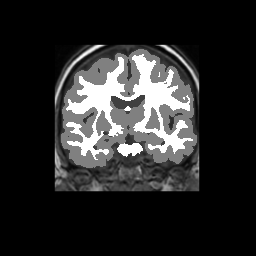

Accuracy is reported as Dice overlaps between a tool's segmentation and the Internet Brain Segmentation Repository (IBSR) manual segmentation for each of the 18 IBSR subjects. The inter-tool comparison (on the left below) shows the median Dice coefficient for each tissue class. The overlaps for FSL (from which the median values are drawn) are shown in the plot on the right.

Overlap coefficients for each tissue class are shown here for each IBSR subject. Select a subject below to see the FSL results compared to other tools.